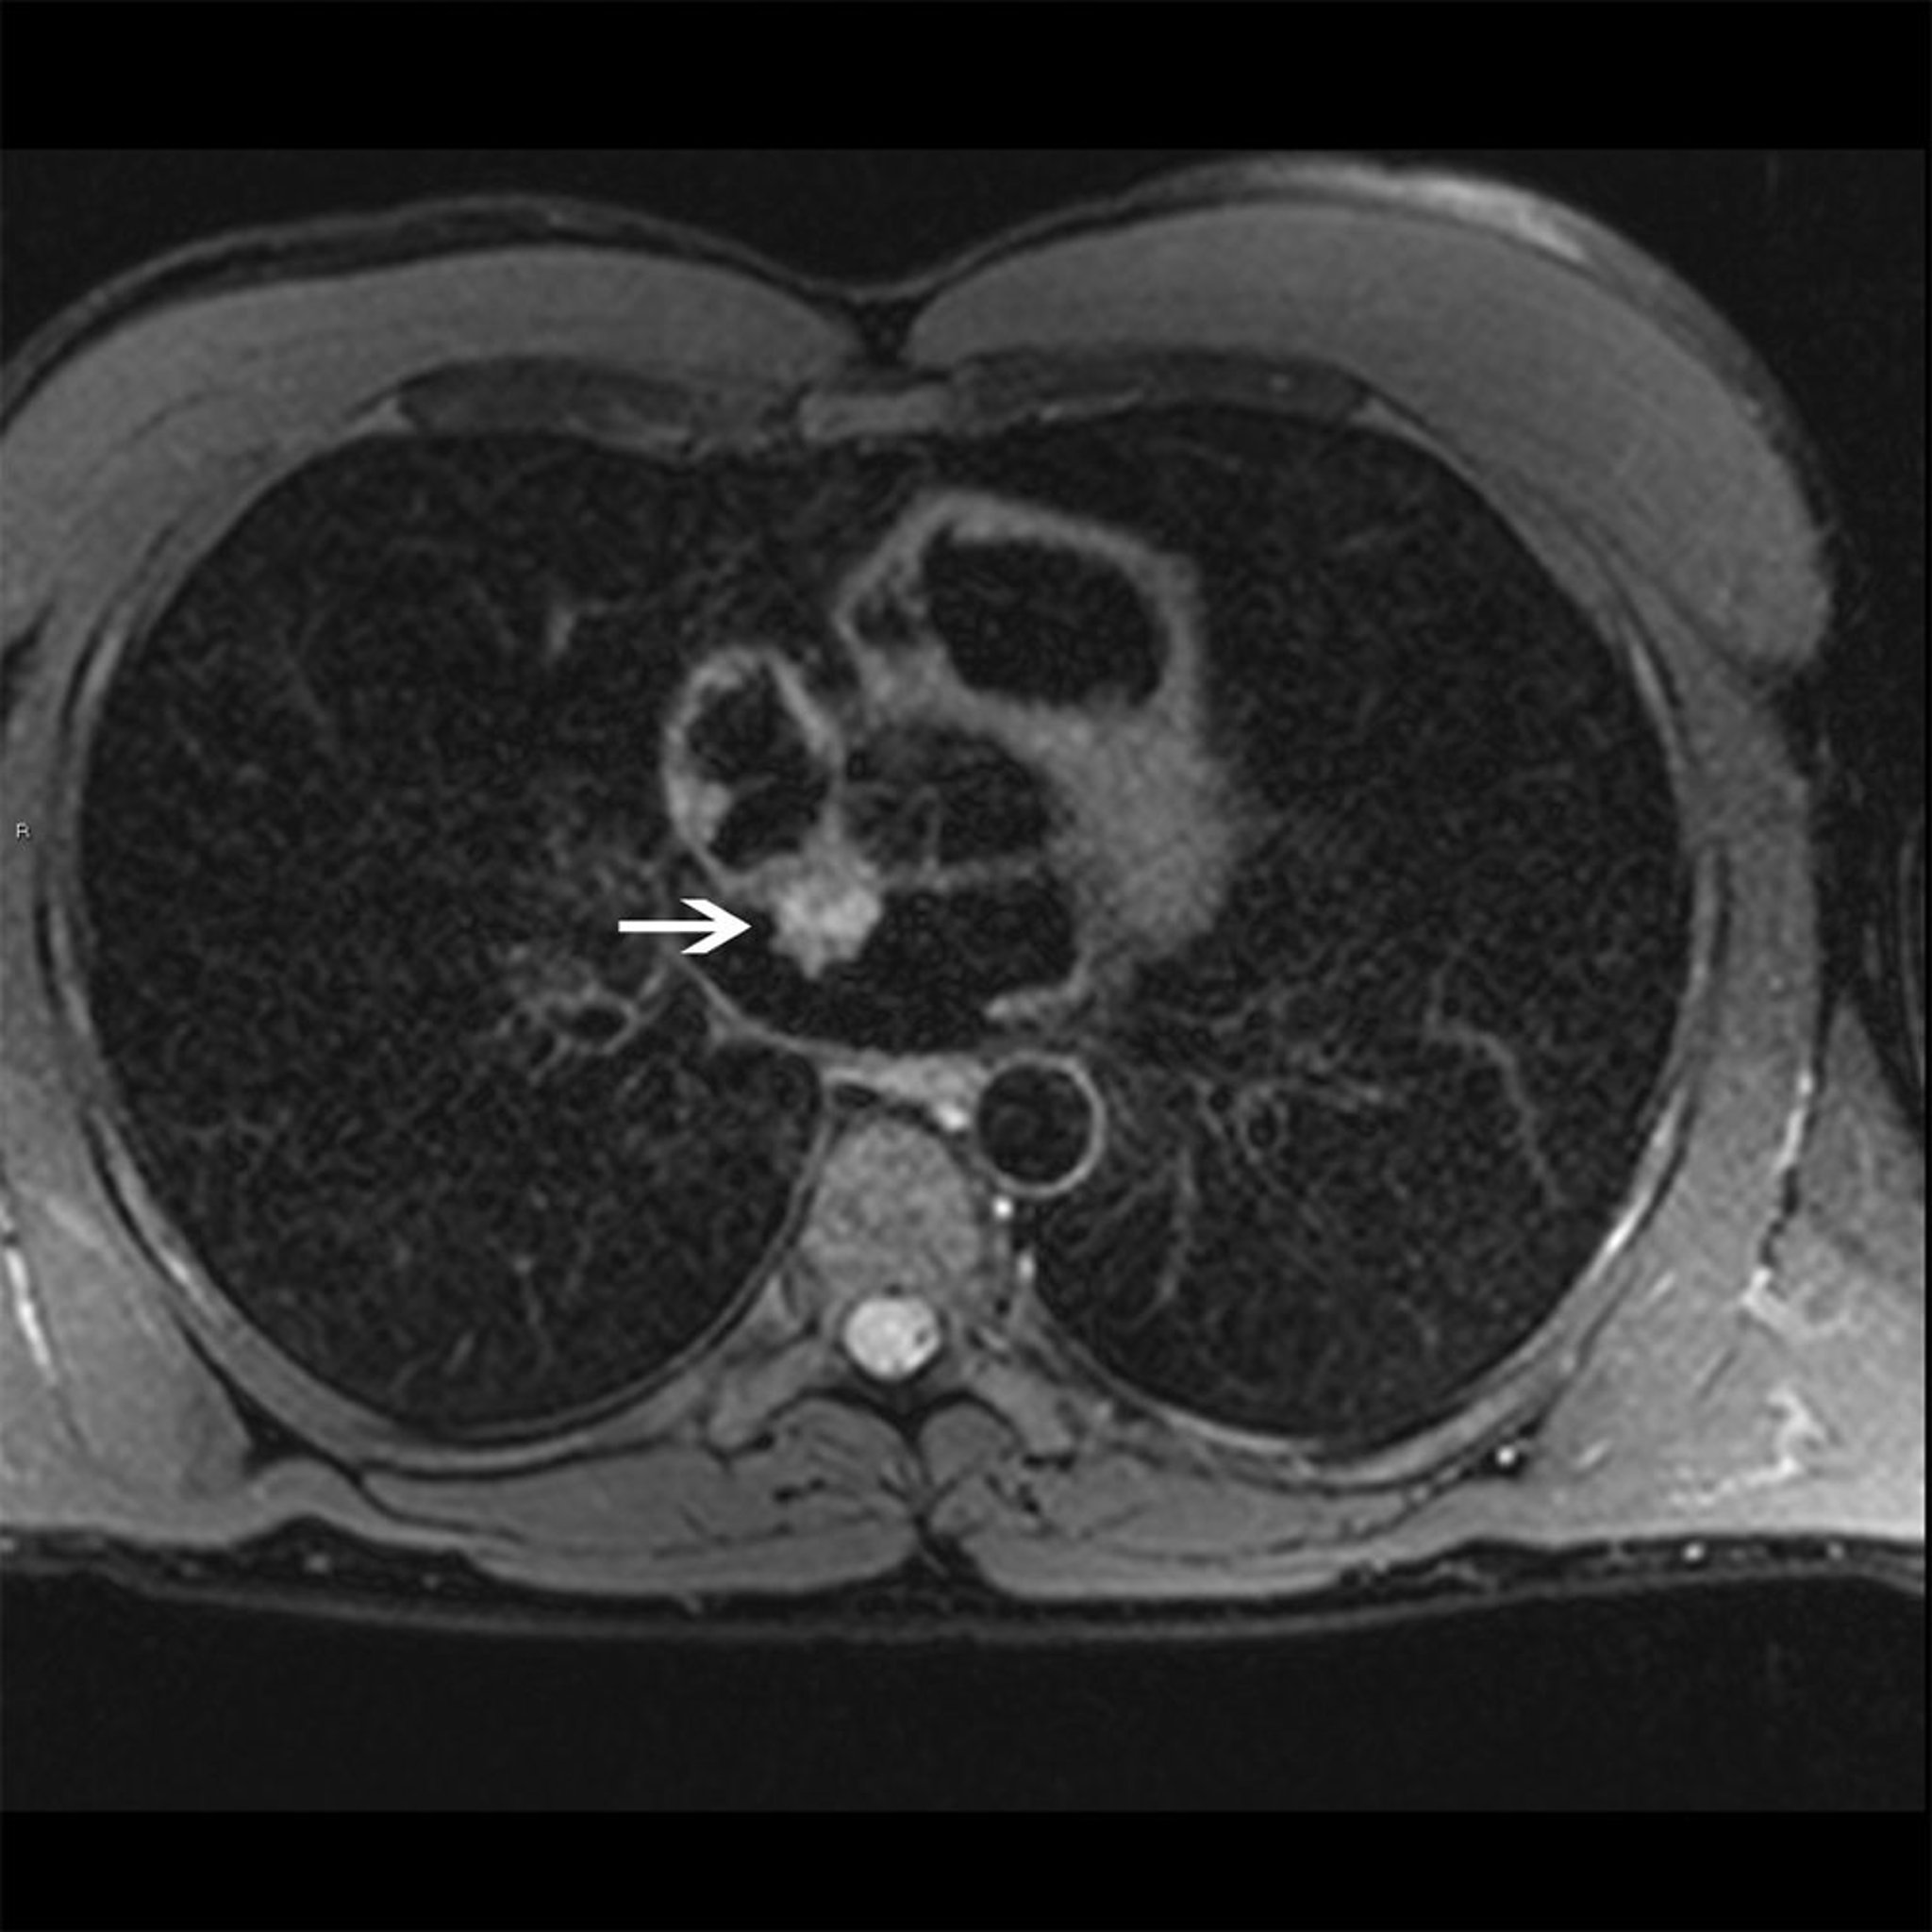

Миксома предсердия (МРТ сердца)

На данной МРТ сердца показана миксома левого предсердия (стрелка), которая является гиперинтенсивной на Т2-взвешенном изображении, что является характерным для миксом.